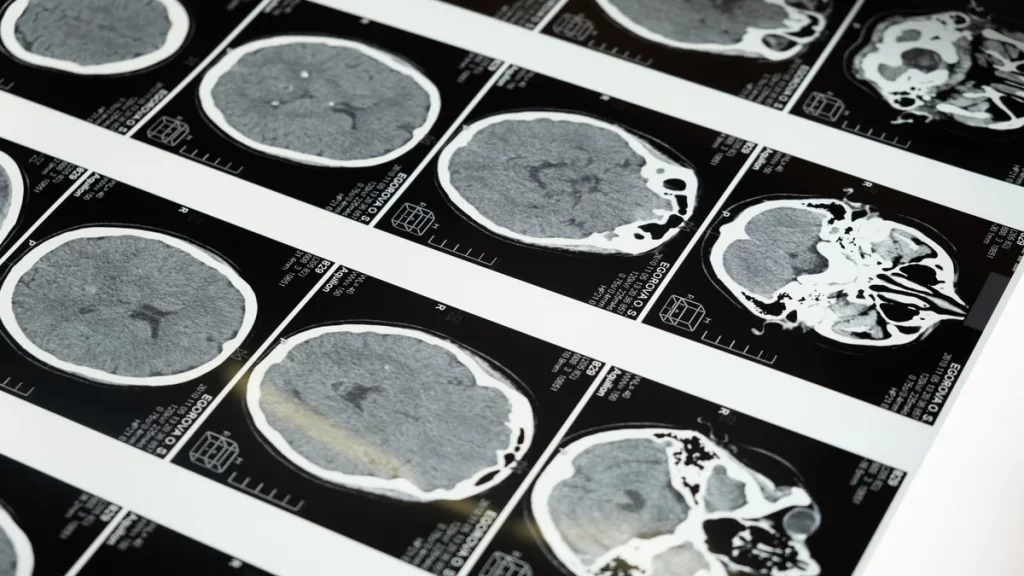

One of the most important tools of neurotechnology is neuroimaging, which allows scientists to visualize the structure and function of the brain in vivo, or in living organisms. Neuroimaging techniques, such as magnetic resonance imaging (MRI), positron emission tomography (PET), and functional MRI (fMRI), can reveal the location, size, and activity of different brain regions, as well as the connections between them. This information is essential for understanding the neural basis of perception, cognition, emotion, and behavior, as well as for diagnosing and monitoring brain disorders such as Alzheimer’s disease, schizophrenia, and depression.